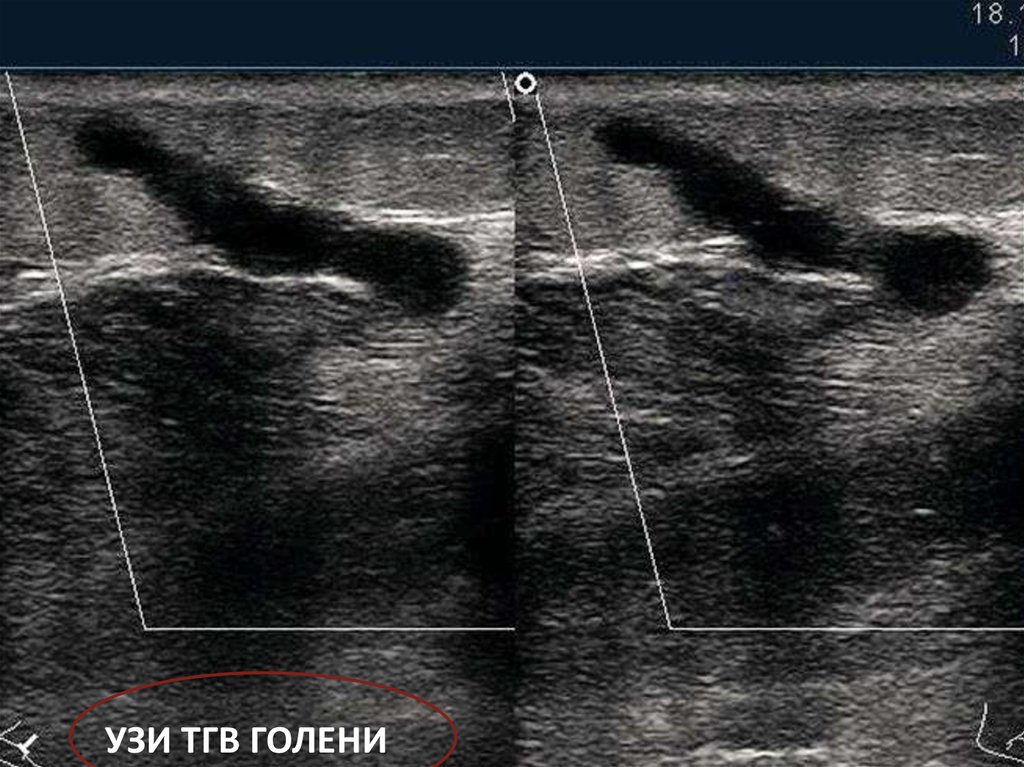

УЗИ ТГВ ГОЛЕНИ